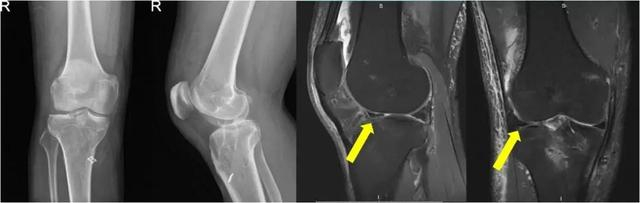

近期,同济大学附属同济医院骨关节外科中心程飚主任接诊了多位半月板缺失的年轻患者。患者冯某某,男性,41岁,4年前因右膝前交叉韧带断裂+半月板损伤,于当地医院行关节镜下右膝ACL重建术+半月板切除术。在半年前患者自觉右膝关节疼痛,活动时加剧,慕名来到上海市同济医院骨关节外科中心/运动医学科找到程飚主任团队,程飚主任经过仔细询问病情,全面查体后给予完善了右膝关节MRI,结果显示右膝关节外侧半月板缺失,外侧间隙狭窄,伴有轻度骨性关节炎出现。

术前影像学资料显示患者外侧半月板缺失,

外侧间隙狭窄